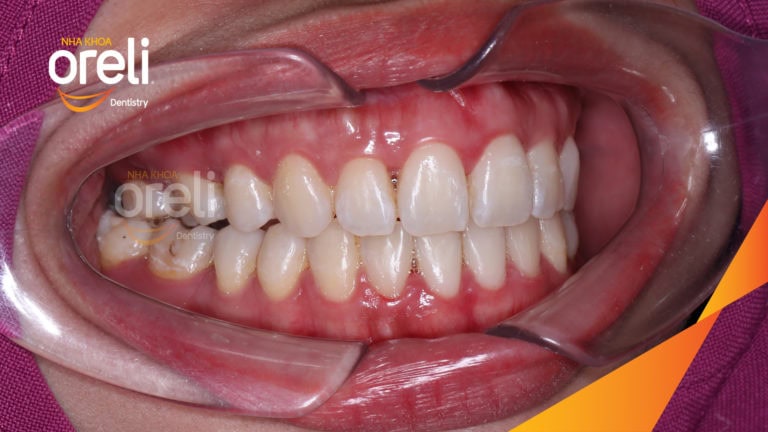

Ca niềng răng đặc biệt: kéo răng 7, 8 thay thế 3 răng 6 bị hư tại Oreli Niềng răngDi gần răng 7 8 Xem thêm